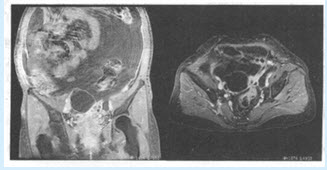

患者,女,55岁。腹胀、腹痛3个月。患者自觉腹胀明显,并觉隐痛,食欲欠佳,查体:腹膨隆,移动性浊音阳性,附件区扪及肿块。无肝病史,实验室检查未见异常。

(多选题)患者做如下检查,你的诊断是()

A:卵巢囊肿

B:卵巢囊腺癌十腹水

C:卵巢囊腺癌伴腹膜转移

D:卵巢囊腺瘤

E:巧克力囊肿

F:卵泡

(多选题)你的诊断依据()

A:附件区见囊性肿物影

B:囊壁内见小壁结节

C:增强后腹膜呈结节性强化

D:大量腹水

E:侵犯子宫

F:以上均不对